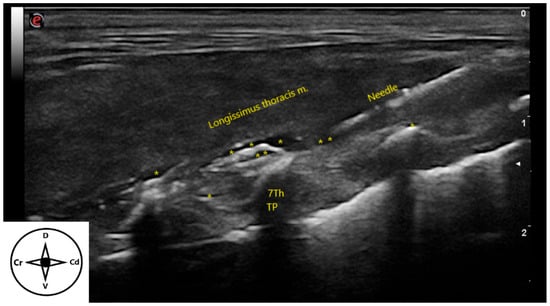

3.2. Ultrasound-Guided Technique